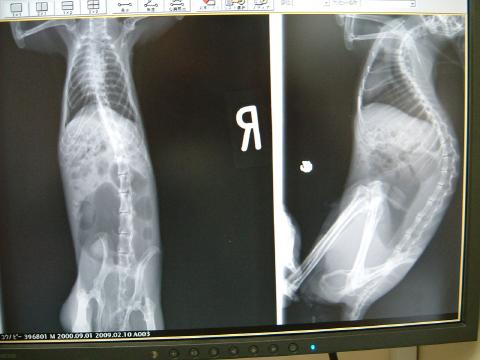

検査・・・レントゲン検査

頭部の写真では、口腔内においてスパイク状に伸びた臼歯過長が認められました。

また、臼歯根尖周囲の石灰化と、歯冠の消失も見られました。

全身においては、胃~盲腸にかけて多量のガス像、とくに盲腸内が重度でした。